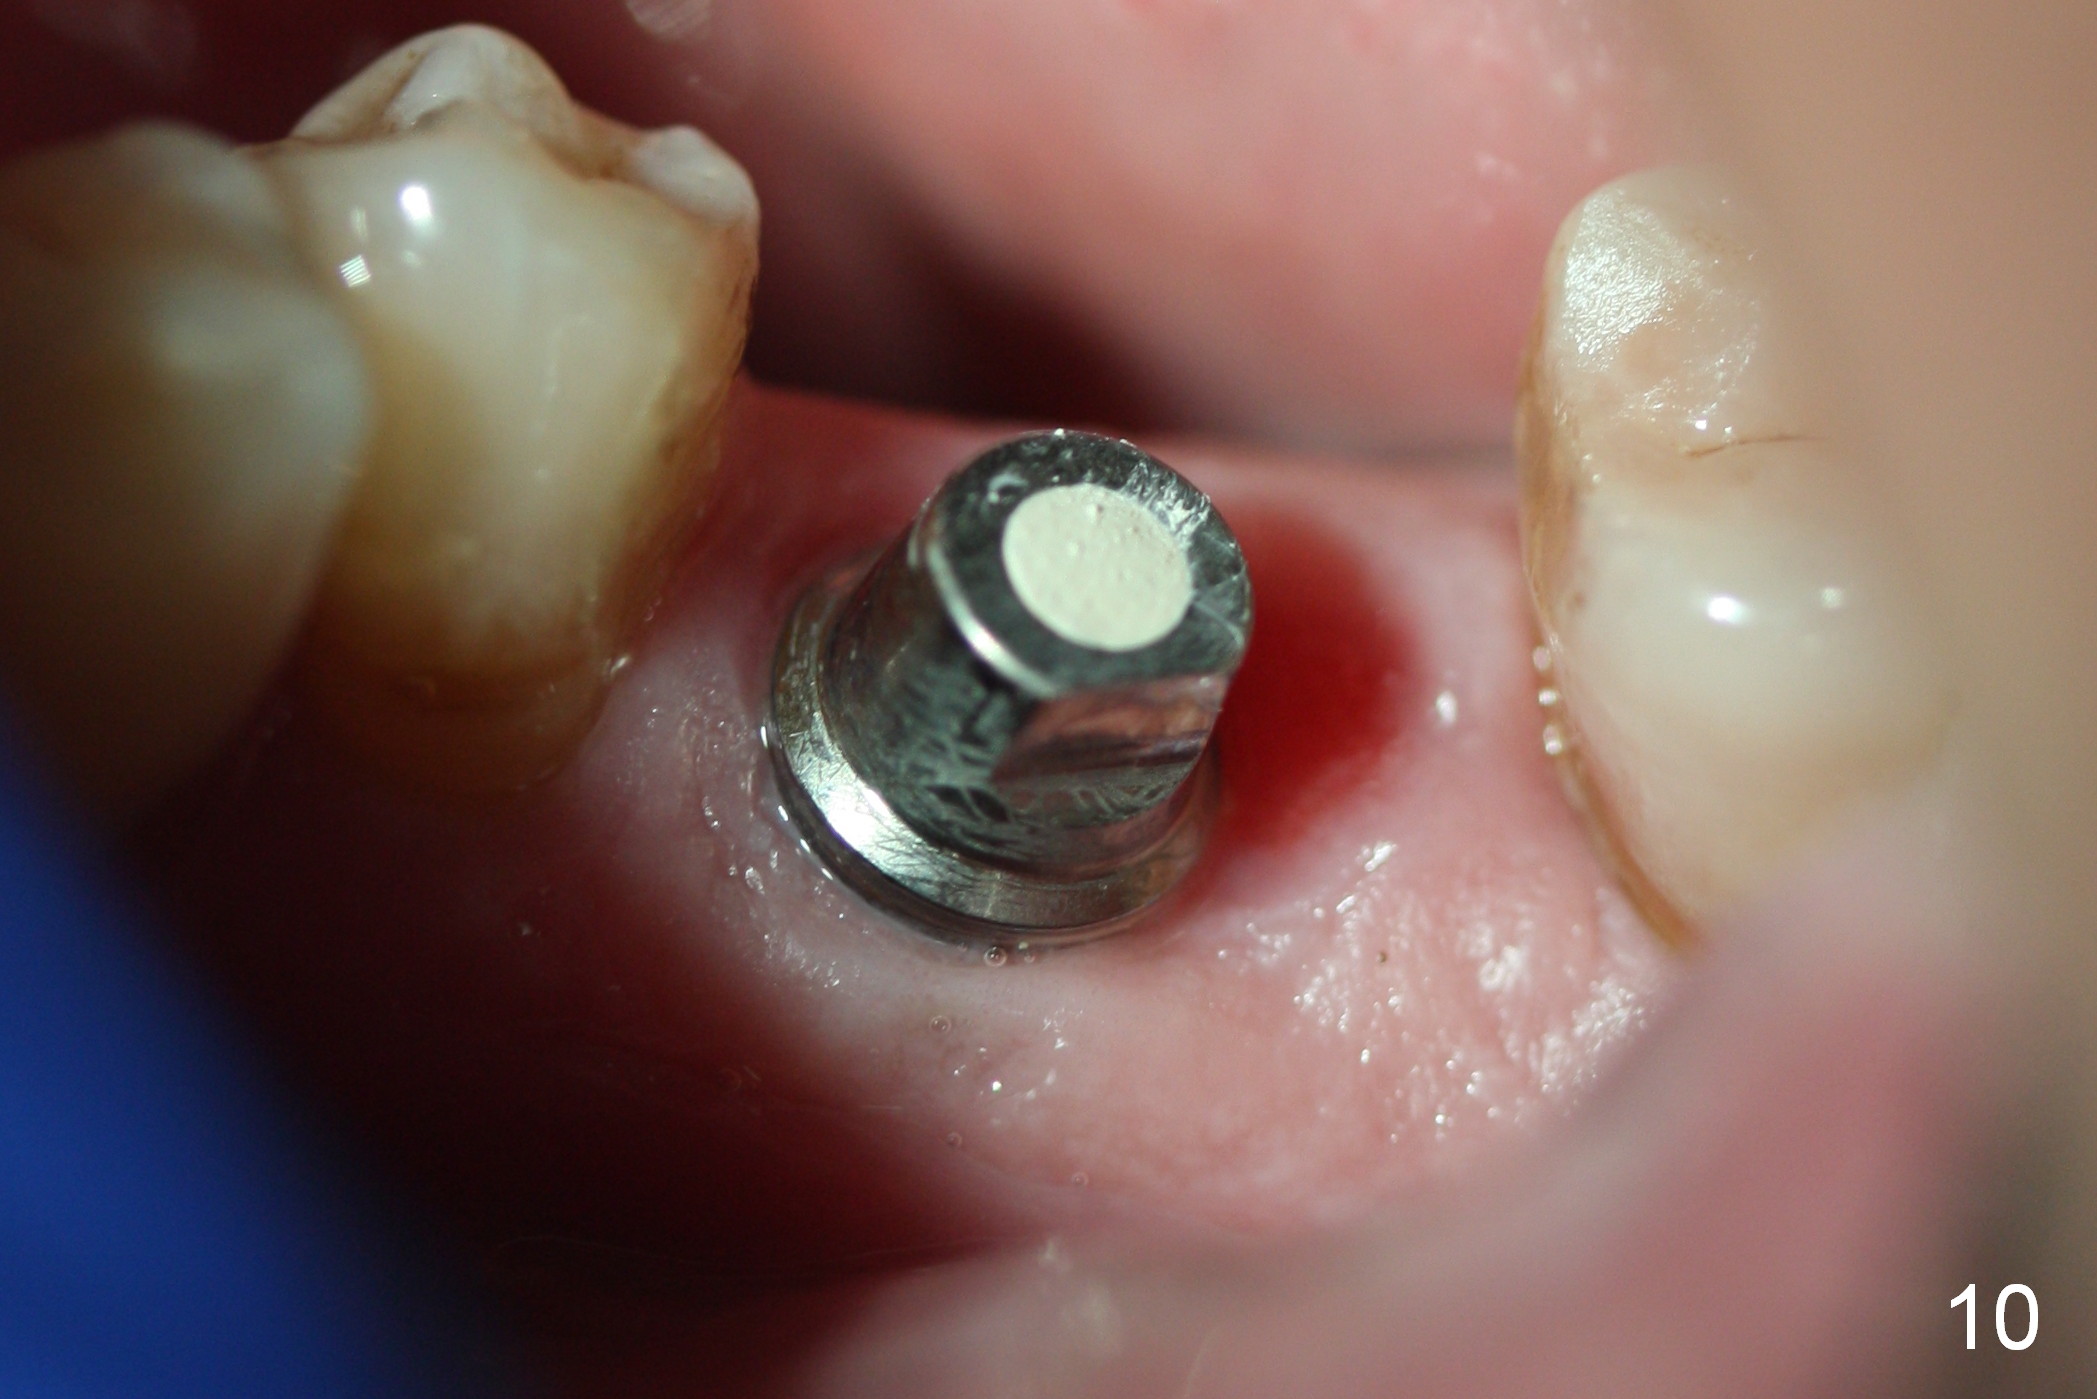

When the patient returns for final restoration 4 months postop, the soft tissue around the implant heals with distinct abutment margin (Fig.10). It is easy to take impression. This is due to the presence of the immediate provisional. The bone density in the original mesial (Fig.11 <) and distal (D) sockets increases, suggesting osteointegration. Eight months later (1 year postop (#19)), the tooth #18 becomes symptomatic and is extracted and replaced by an implant (Fig.12). The distal socket at #19 has disappeared, while the plateau of the implant is covered by the bone (^).